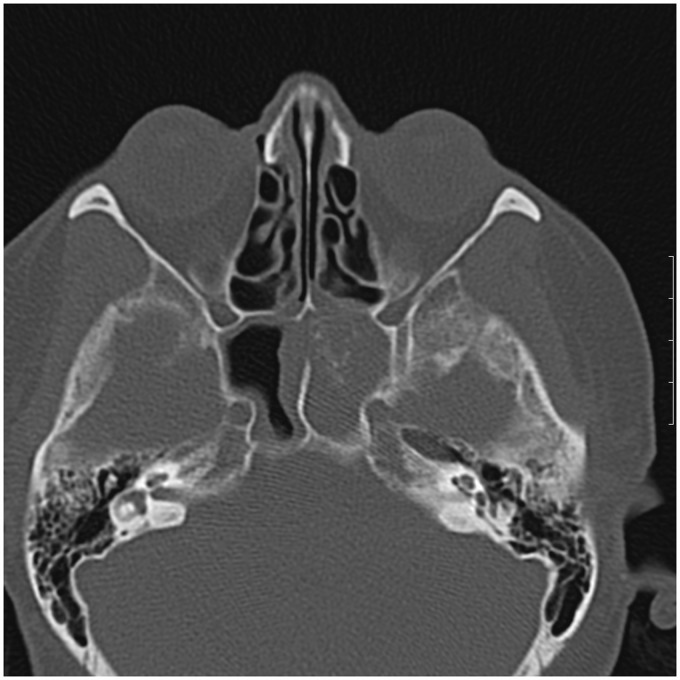

一例孤立的蝶骨真菌鼻窦炎在一个老年糖尿病患者被描述。偶然发现位于鞍区共存的肿块病变。这两个实体的重合代表了潜在的手术灾难,可能导致真菌感染的直接颅内扩散。

A case of isolated sphenoid fungal sinusitis in an elderly diabetic patient is described. A coexisting mass lesion located in the sellar region was detected incidentally. Coincidence of these two entities represents a potential surgical disaster which may result in direct intracranial spread of fungal infection.